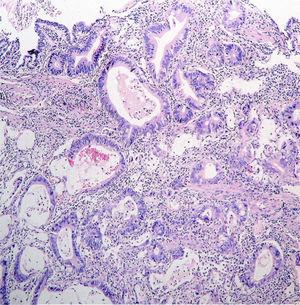

Adenocarcinoma gástrico

El adenocarcinoma gástrico representa una de las principales causas de mortalidad por cáncer a nivel global, ubicándose como la tercera causa más común de muerte por esta enfermedad. Esta posición…